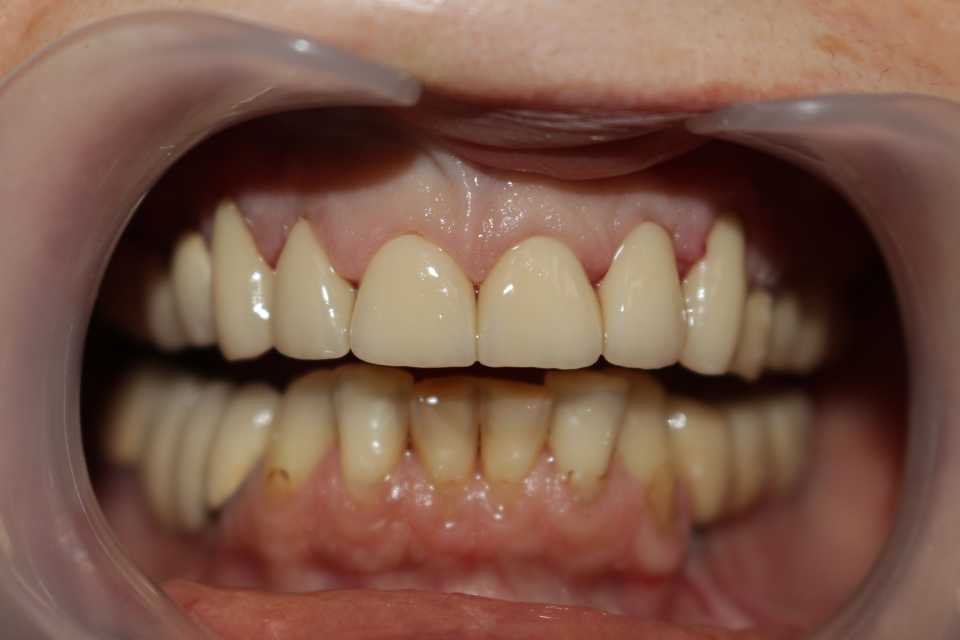

Cazul a fost rezolvat cu ajutorul coroanelor de tip ceramică pe suport de zirconiu, in 2 sedinte, cu slefuiri minim invazive, dintii ramanand vitali.

Coroanele dentare au scopul de a readuce la forma naturală și la starea de normală funcționare, un dinte deteriorat.